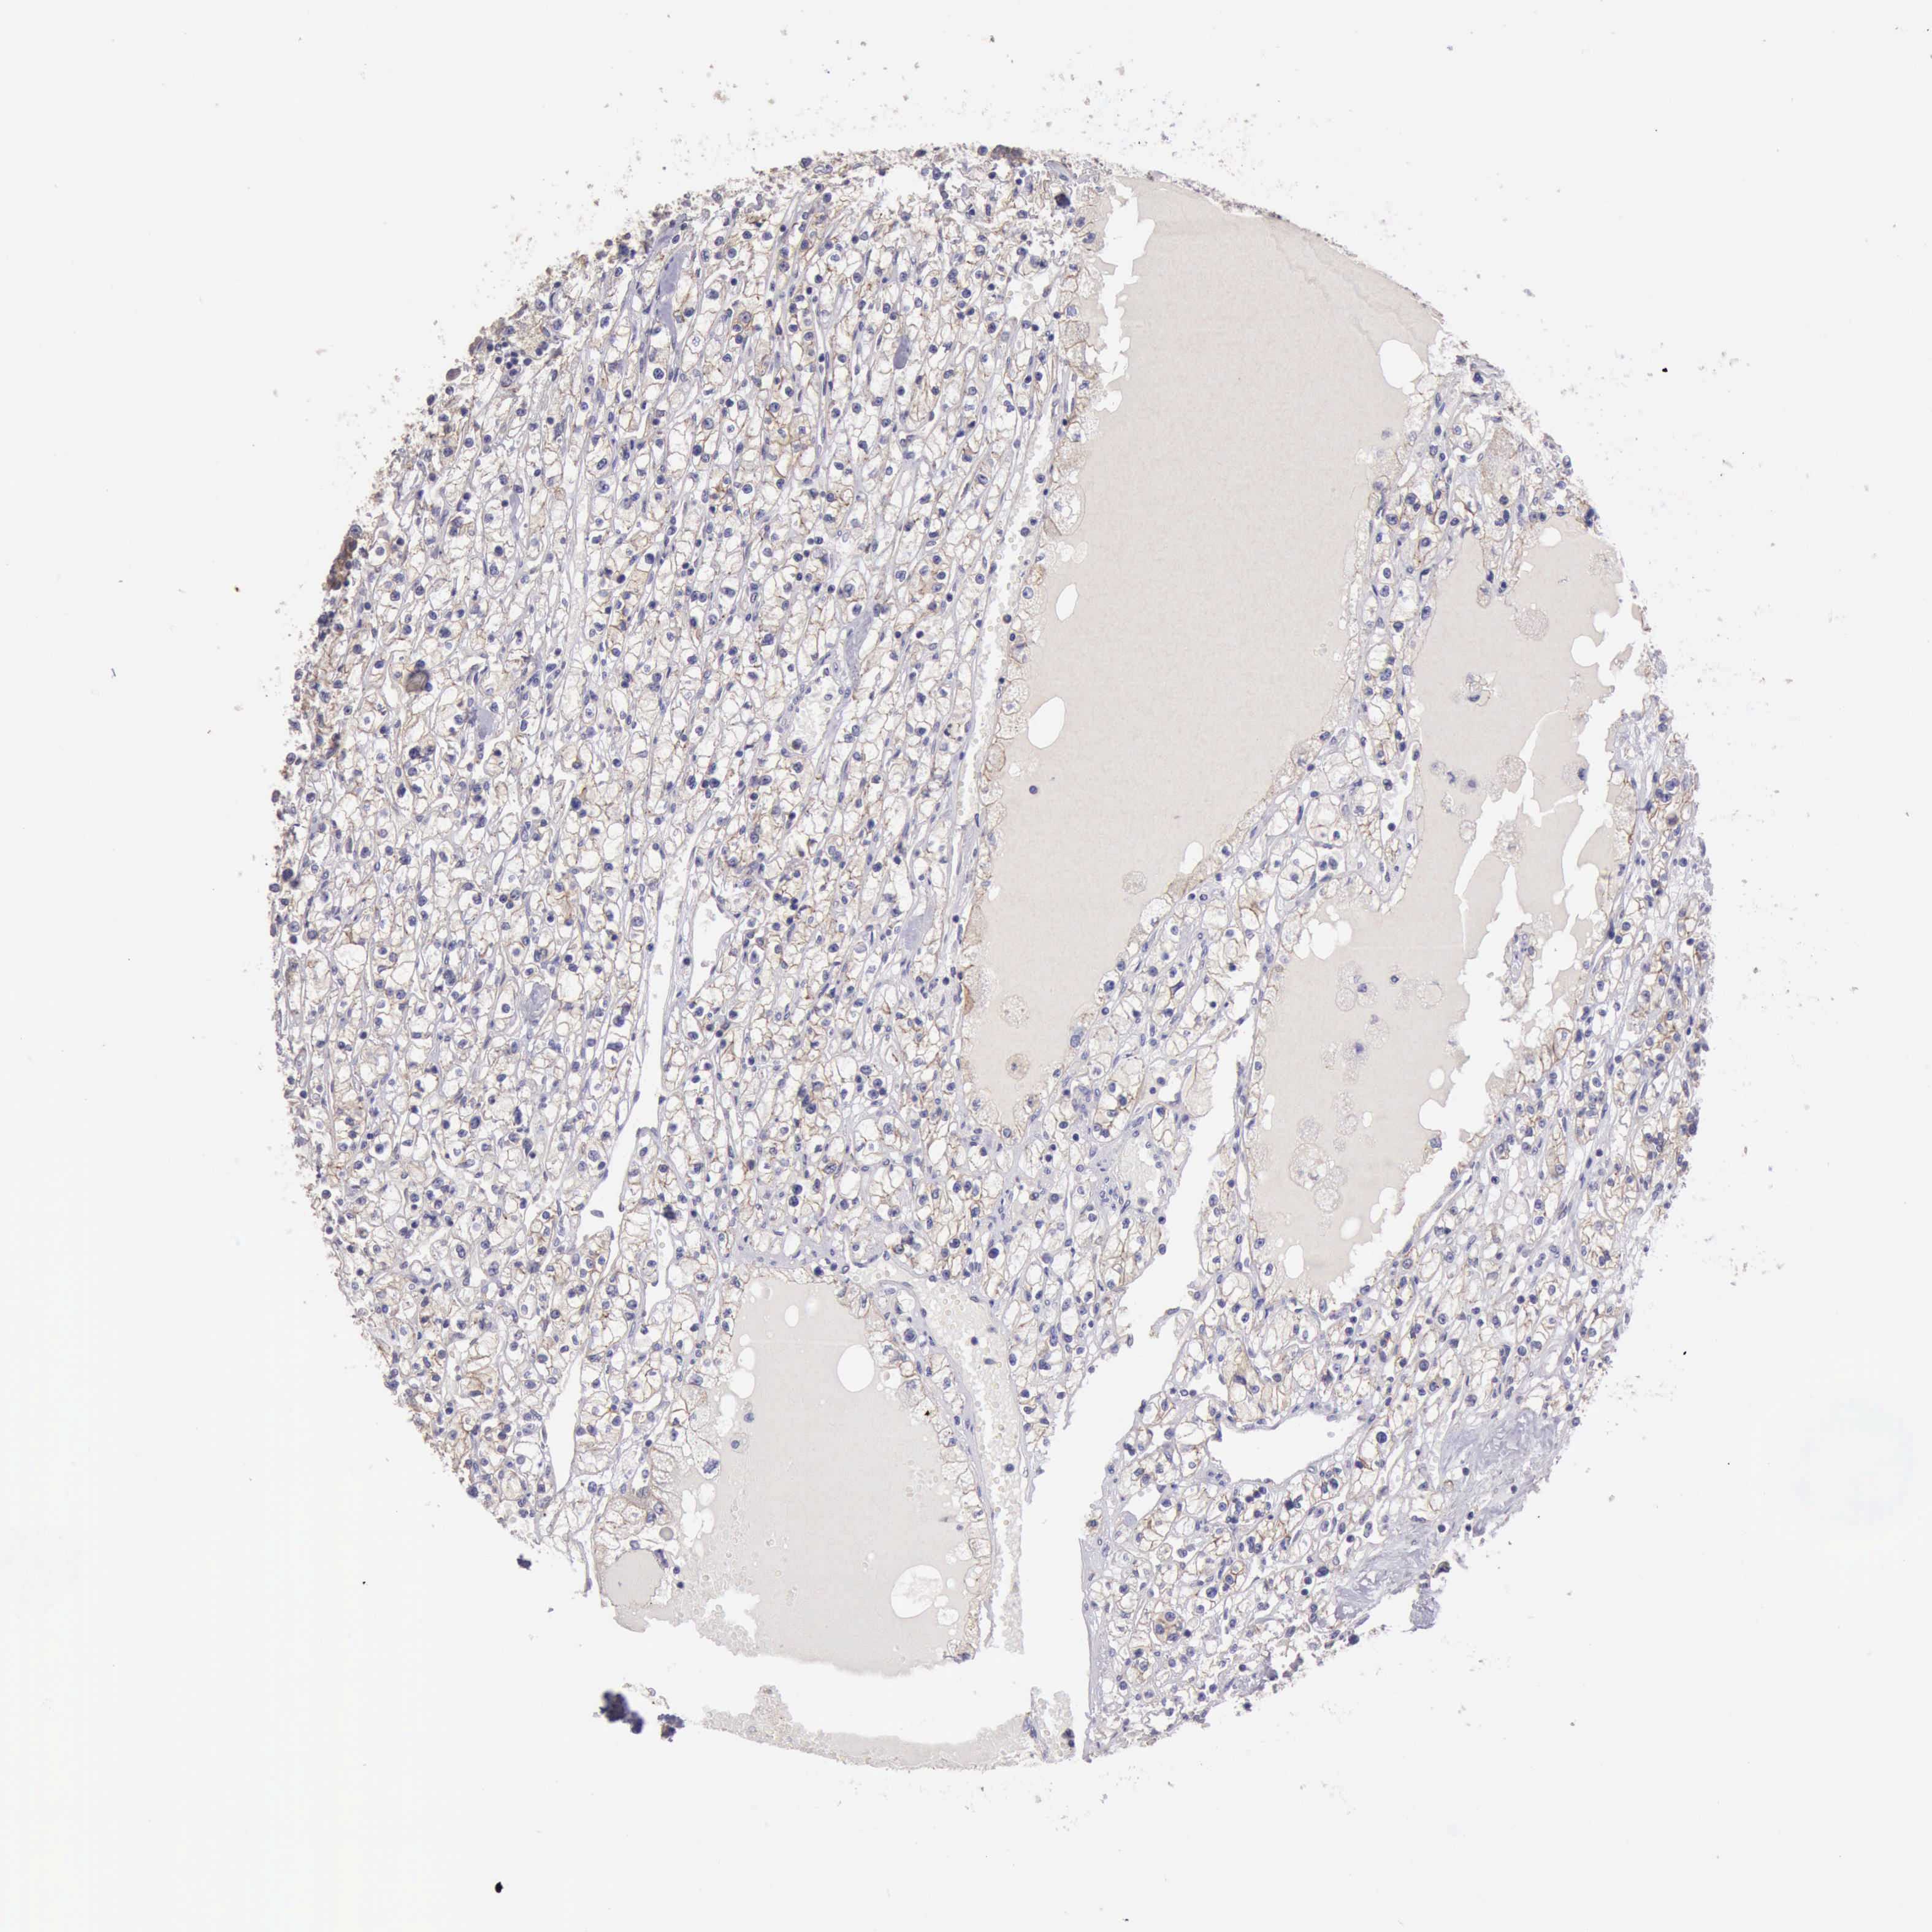

KICH TCGA KIRC TCGA KIRC VALIDATION KIRP TCGA PROTEIN RCC CPTAC PROTEIN EXPRESSION